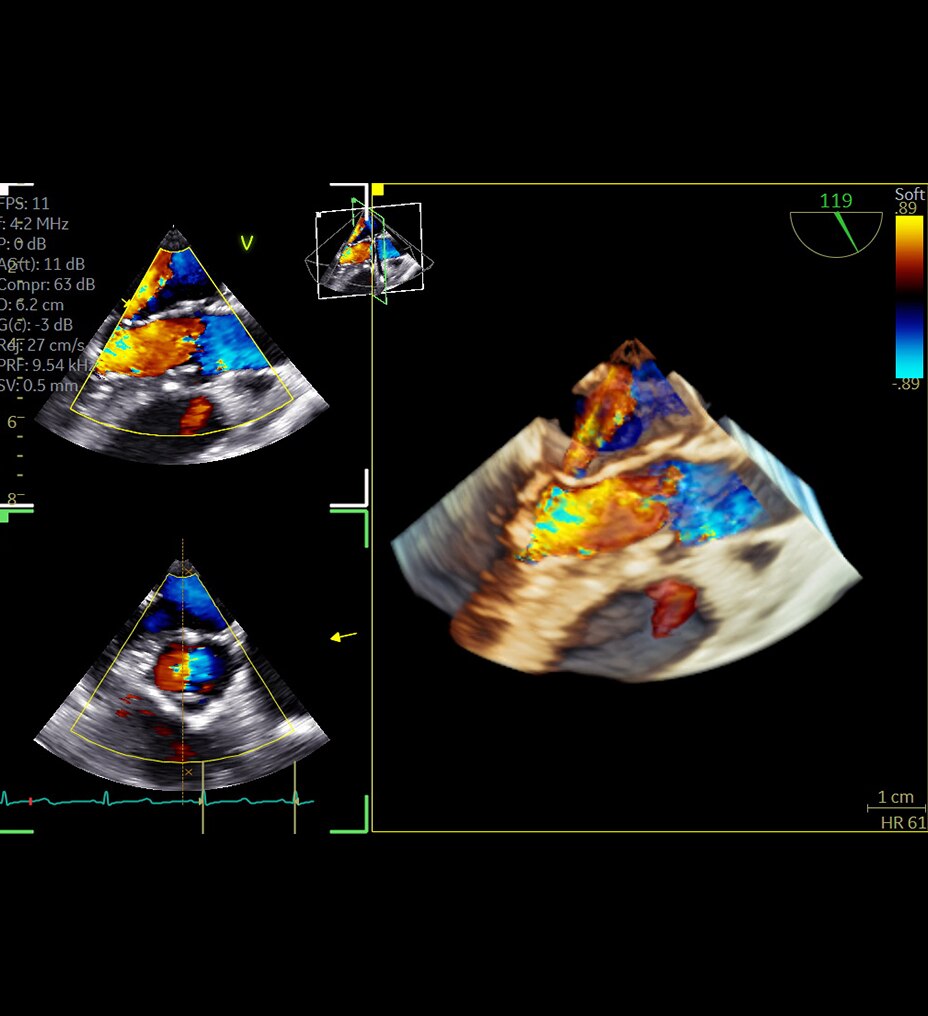

Üstün görüntü kalitesi

Daha net görüntüler daha kolay tanılar anlamına gelir ve derin öğrenme teknolojimiz AIR™ Recon DL ile olağanüstü kalitede görüntüleri daha hızlı elde edebilirsiniz. Çok çeşitli anatomiler için en net sonuçları sağlayarak MR görüntülerini görüntüleme biçiminizde devrim yaratır.

Ayrıca, göz yorgunluğunu azaltabilen okunması kolay, yüksek kaliteli taramalarla elde ettiğiniz görüntülerin kalitesinden daha emin olarak oluşturulan raporların daha iyi bir genel deneyime sahip olmasını sağlayabilirsiniz.